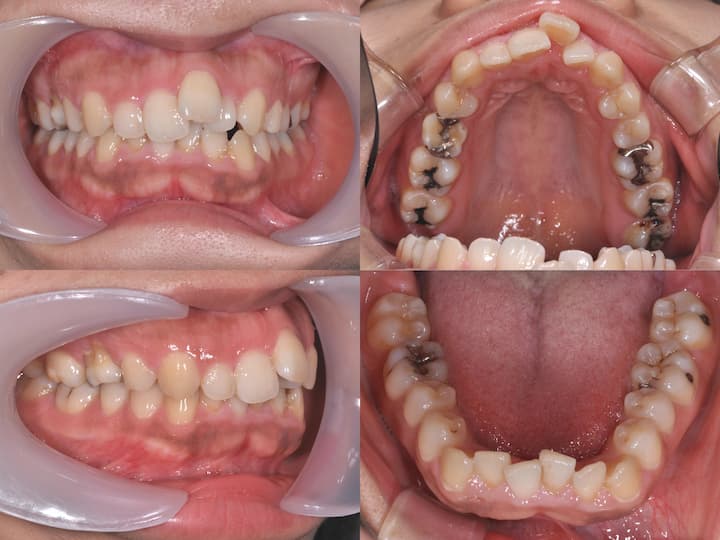

治療結果

上顎大臼歯の圧下により下顎骨のアンチクロックワイズローテーションが誘導され、口唇部の突出感は著明に改善されました。

また、叢生も解消され、AngleⅠ級臼歯関係を維持したまま、機能的かつ審美的に優れた咬合状態を獲得することができました。

臼歯部の咬合も良好に保たれ、患者様からも高い満足度をいただいております。

本症例は、下顎骨の後方位を伴うハイアングル症例であり、口唇部の突出感が主訴の一つでした。

このような症例では、上顎大臼歯の圧下による下顎骨のアンチクロックワイズローテーションが有効な治療戦略となります。

i-stationを用いた確実な固定源の確保と、フルサイズTMAワイヤーおよびパラタルバーによる緻密な咬合管理により、臼歯部のオープンバイトを生じることなく、大臼歯の圧下を達成することができました。

その結果、AngleⅠ級臼歯関係を維持しながら、口唇部の突出感を改善し、優れた治療結果を得ることができた症例です。